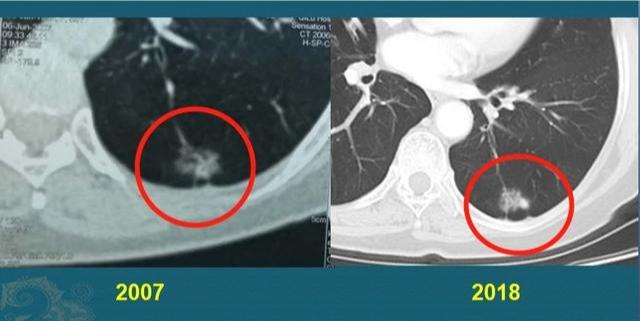

这是一位成年男子,干咳一周发现右侧肺癌,2.2厘米,支气管镜淋巴结穿刺以及痰液检查,明确为浸润性肺腺癌,伴有多发转移。

已经无法做根治性手术,选择放弃治疗听天由命,结果仅仅过了8个月,复查CT显示肿瘤增大到接近8厘米,速度非常快: